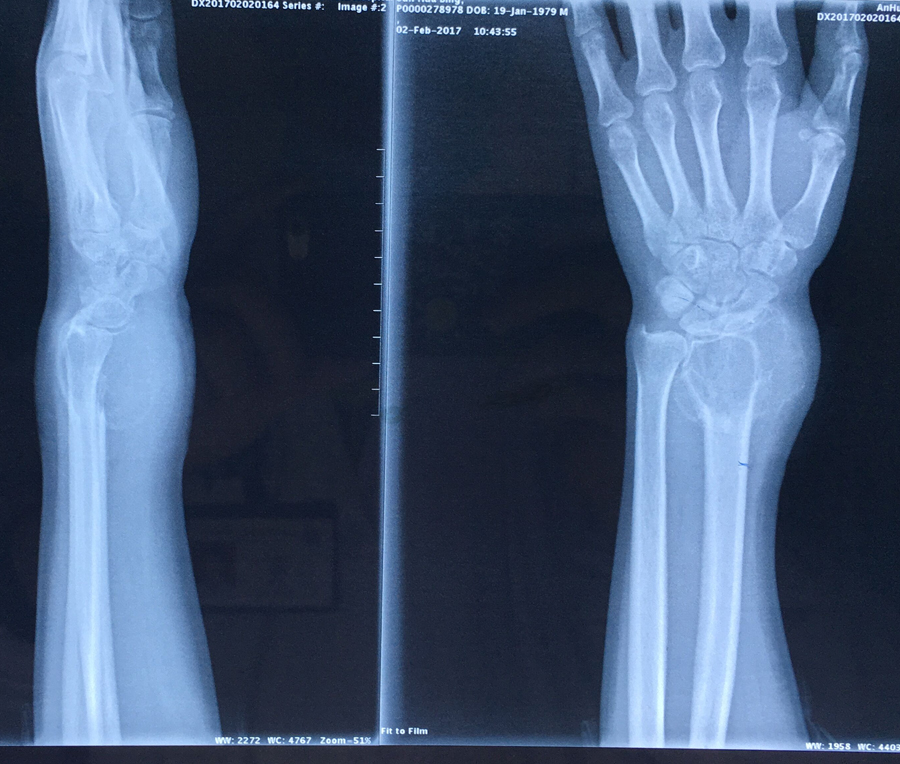

近日,我院关节与骨肿瘤科为一名桡骨远端骨巨细胞瘤Ⅲ级、肿瘤突破间室的男性患者成功实施了肿瘤广泛切除,自体腓骨活骨移植重建桡腕关节术。据悉,对于肢体恶性、侵袭性骨肿瘤,实行广泛外科边界的切除是达到良好的肿瘤学疗效的基础,但这必然会带来肢体结构和功能的更多的丧失。如何既能达到肿瘤的广泛切除,又能最大限度恢复肢体的结构和功能是骨肿瘤外科所追求的目标。肢体结构和功能的生物重建是最接近肢体生理状态的长期有效的重建方式。该方法要求手术者不仅具有精湛的肿瘤外科技术,还要有熟练的显微外科技术,是目前临床上受到普遍推崇的方法。近年来,关节与骨肿瘤科已开展此类手术20多例,取得了良好的效果。